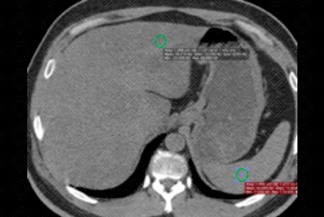

Texto alternativo para a imagem Figuras 1 e 2. Créditos: Dra. Elazir Mota - Rio de Janeiro/RJ

Descrição da lesão: Tomografia computadorizada do abdome, em fase sem contraste venoso. Foram medidos os coeficientes de atenuação hepáticos e esplênicos, com uma diferença entre eles superior a 10 UH, compatível com esteatose hepática (densidade hepática de 28 UH e esplênica de 42 UH).